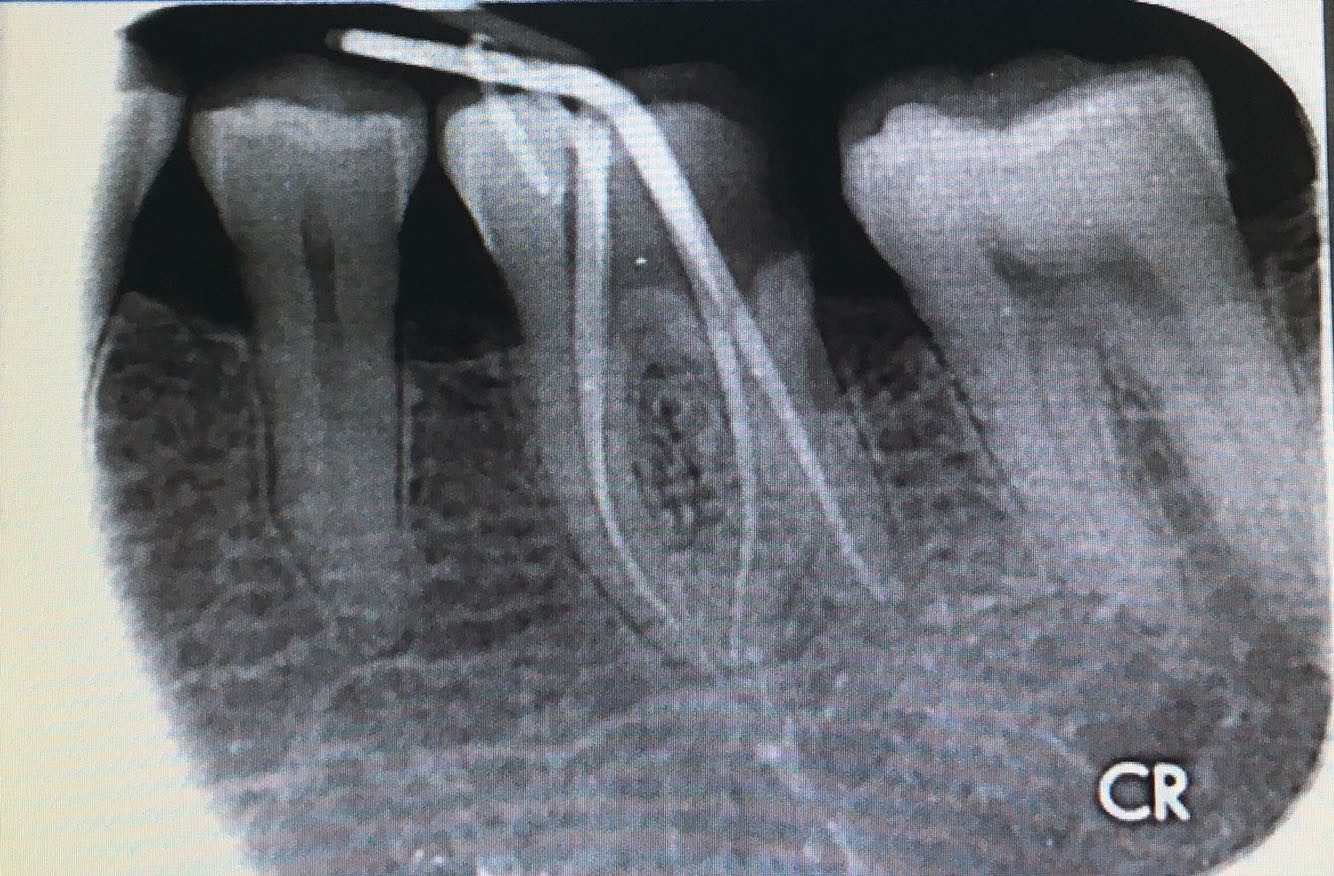

检查:左下 6 合面白色暂封物,冷测无反应,探(-) ,叩(-) ,不松,龈正常,根尖相应粘膜处无红肿及压痛。 X 片示:左下6冠部高密度充填影像与髓腔穿通,根尖周正常,髓腔无钙化,远舌根管弯向近中

处置:左下6 去 ZOE,开髓孔无探痛,揭顶,拔髓,探及 M2D2 四根管,10#锉疏通各根管,测 WL: MB=19mm, ML=19mm, DB=18mm, DL=18.5mm, EDTA下,常规预备至F2,3%过氧化氢和0.9%生理盐水冲洗+超声荡洗根管交替进行。隔湿,干燥根管,氧化糊剂牙胶尖冷侧压充填,ZON暂封。嘱勿用患牙咬物。 2周后复诊,冷(一),叩痛(一),不松,牙龈无红肿,去除暂封物,牙体组织预备,流动树脂垫底填除倒凹,电子影像取模,送CAD/CAM制作高嵌体。 3日后复诊,嵌体配戴,调合,抛光,树脂粘接剂永久粘接。 患者对修复效果满意,交待患者使用注意事项。